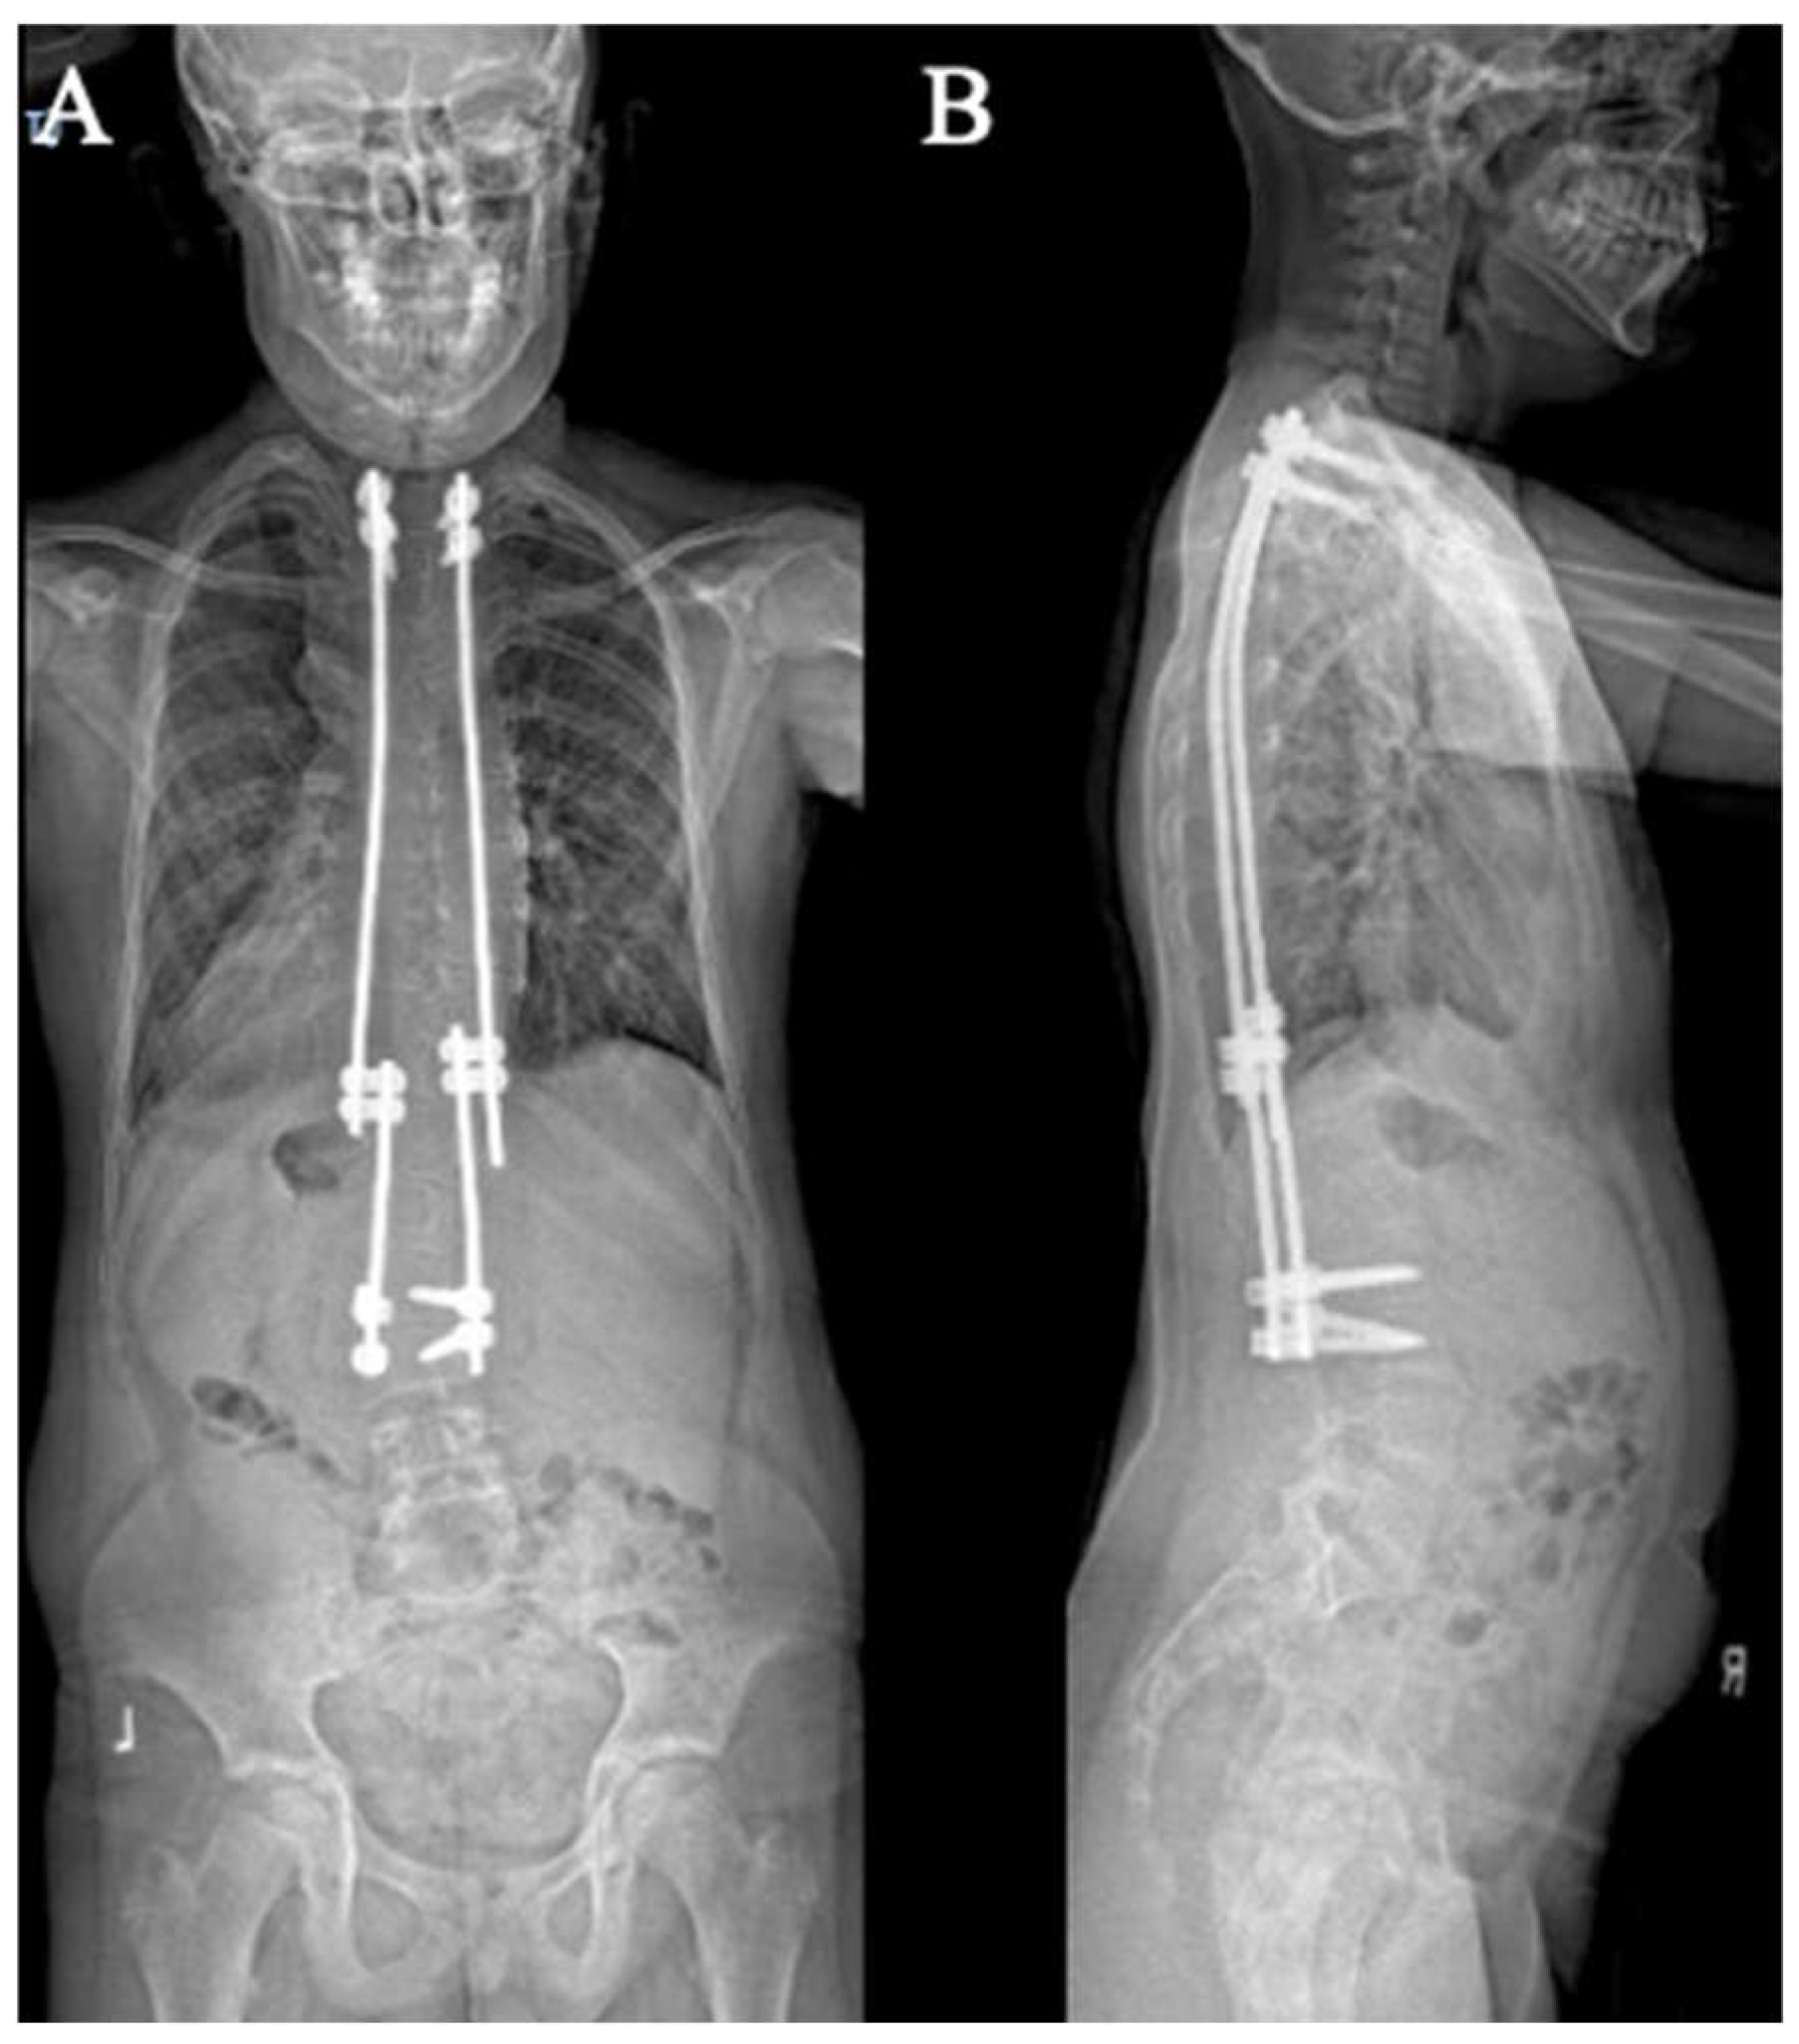

Figure 6.

AP (A) and lateral (B) X-rays demonstrating the construct-to-construct internal distraction technique in a traditional growing rod construct.